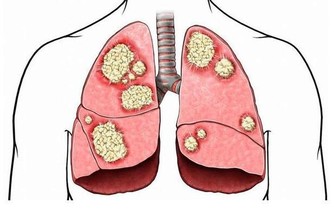

拇指腫脹呈鼓槌狀:容易患先天性心髒病或支氣管擴張等胸部疾病。